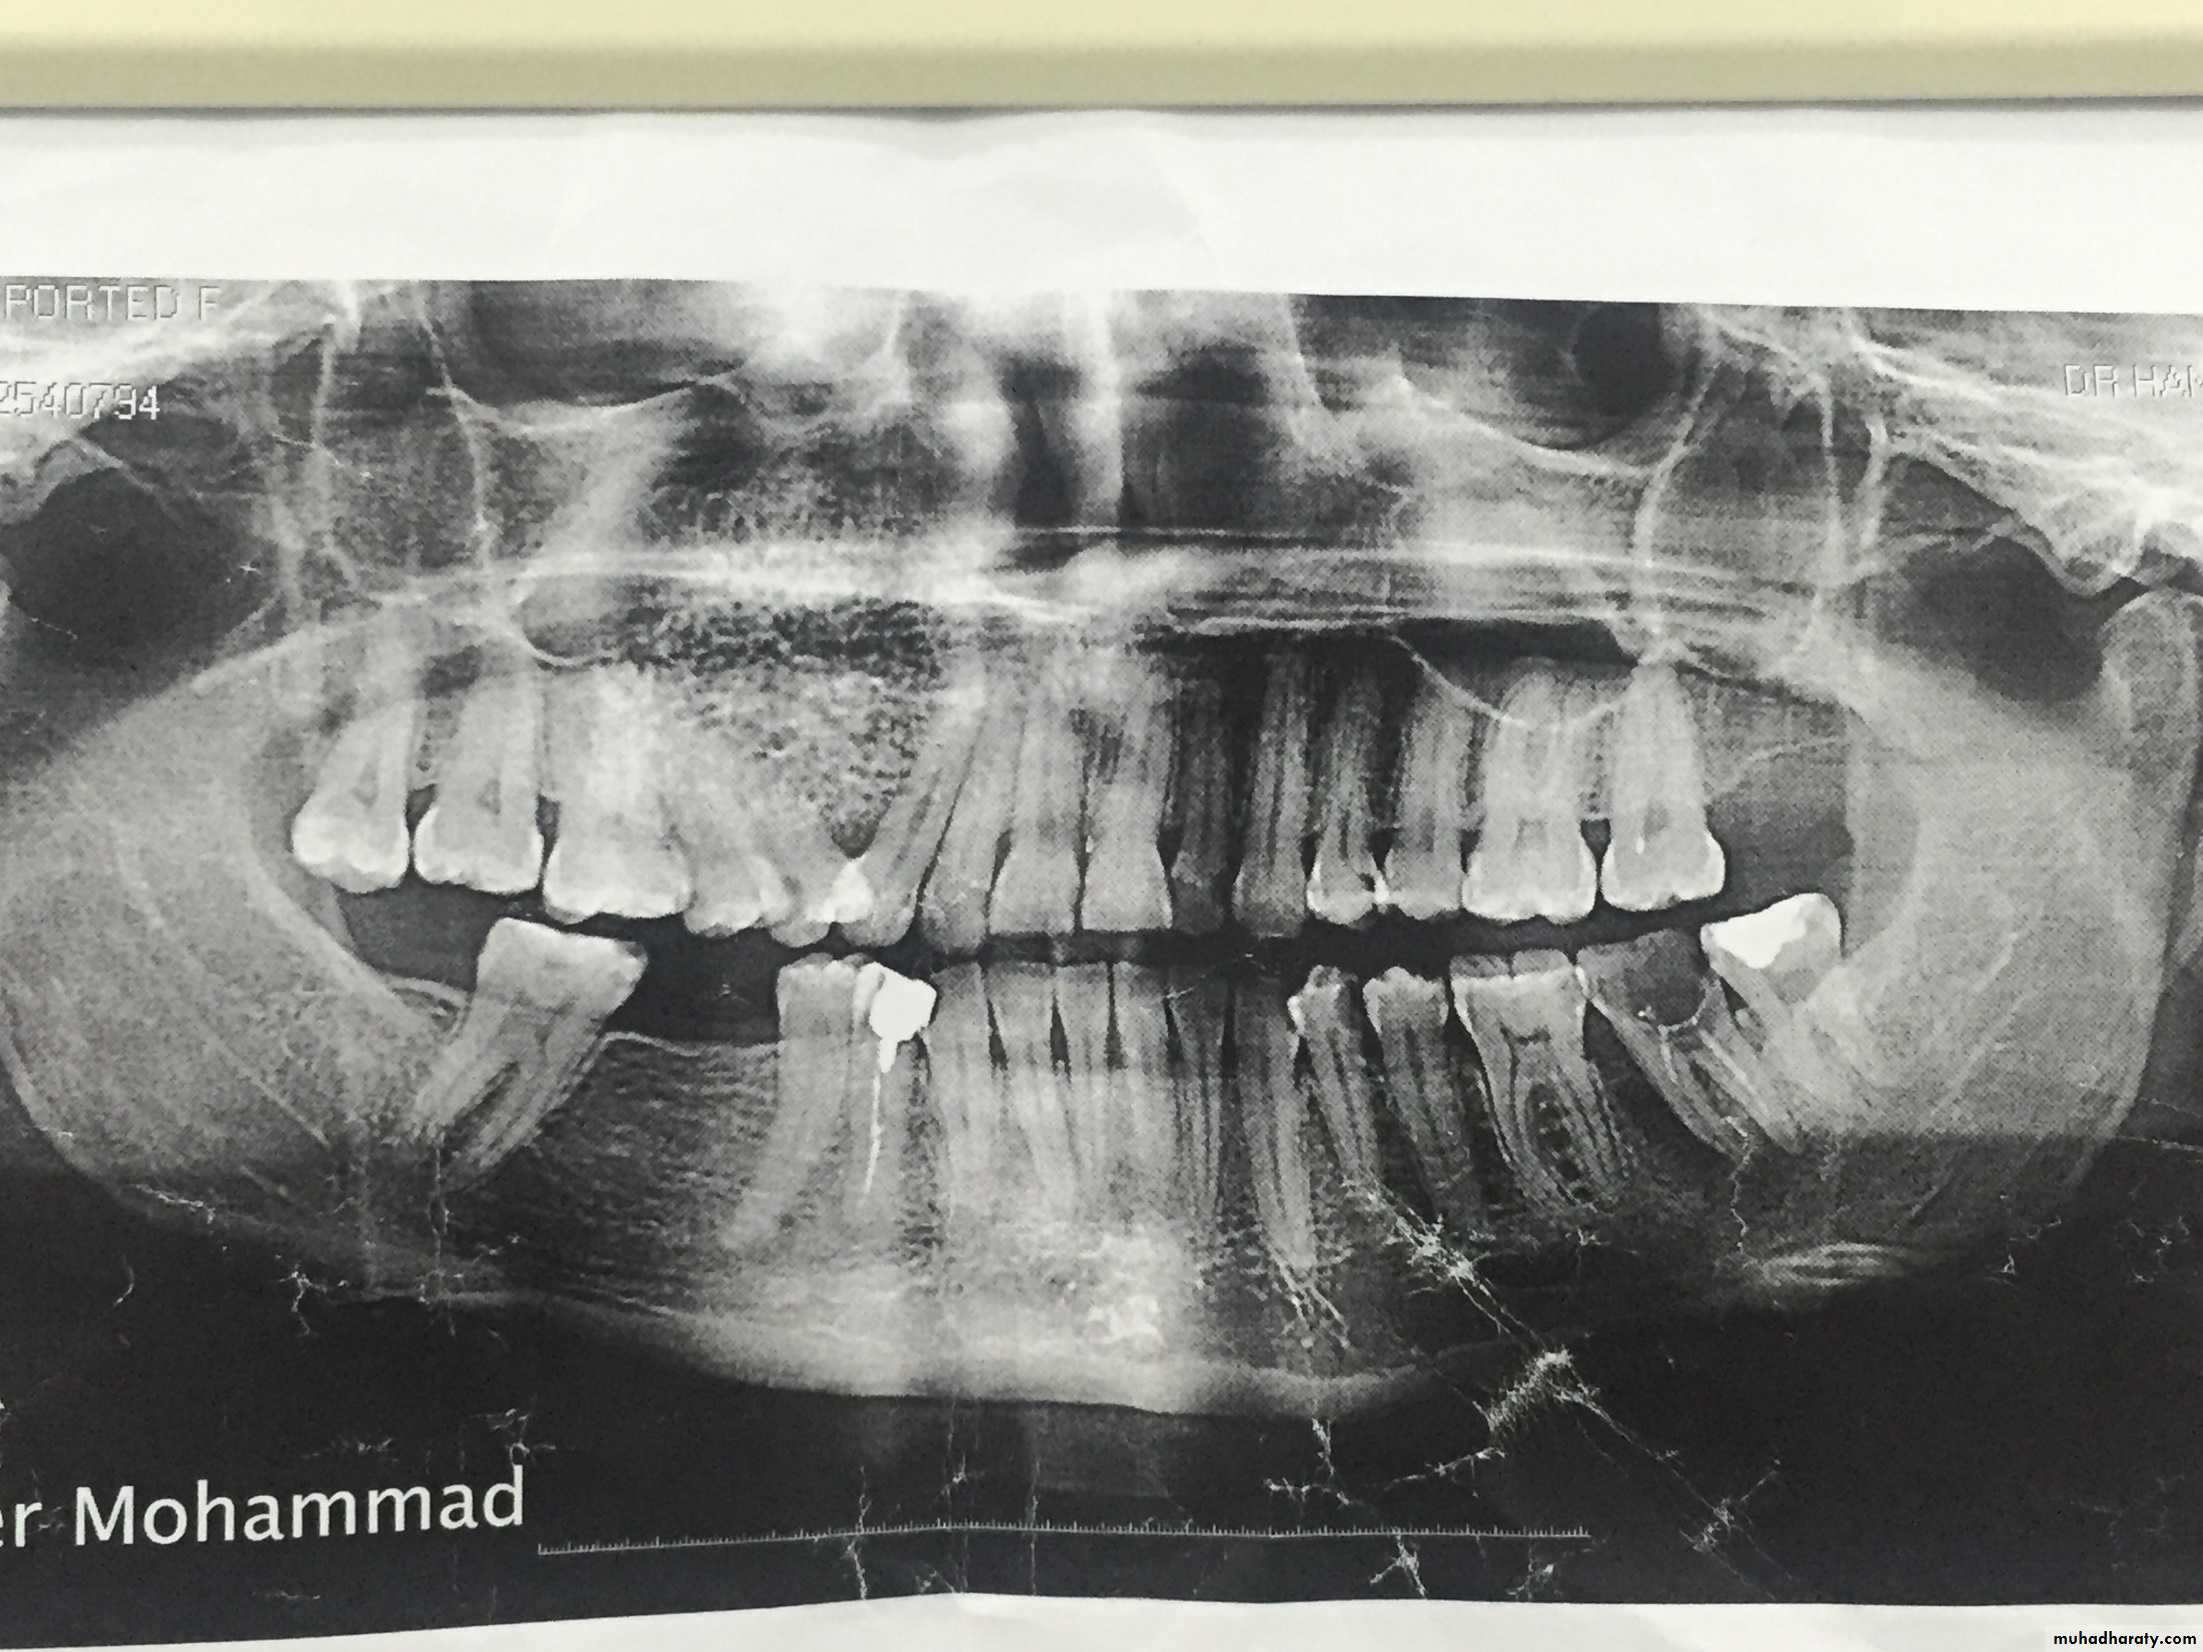

which is a benign slow growing tumor of bone that tends to have its greatest growth in the second decade of life. it is a diffuse poorly differentiated endosteal tumor. replacing the normal spongiosa with fibrous tissues. The enlargement neoplasm may displace teeth and expand cortical plates of the jaw bones.Fibro-osteoma tends to occur more frequently in women than in man and is seen more often in the maxilla than in the mandible. The active fibro-osteoma or ossifying fibroma frequently recurs when surgical excision dose not include . 10 to 12mm margin or when treatment has been instituted at an early age. radical treatment is less likely to lead to a later recurrence. These tumors do not respond favorably to radiation therapy.